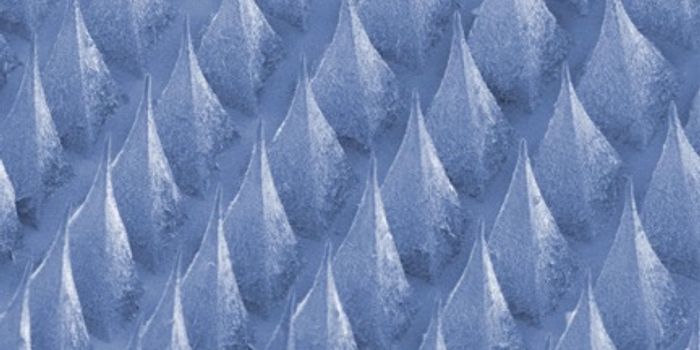

SEP 16, 2021Clinical & Molecular DXForget uncomfortable chest straps or clunky wristbands—thanks to a new innovation in nanotechnology, your t-shirt ...